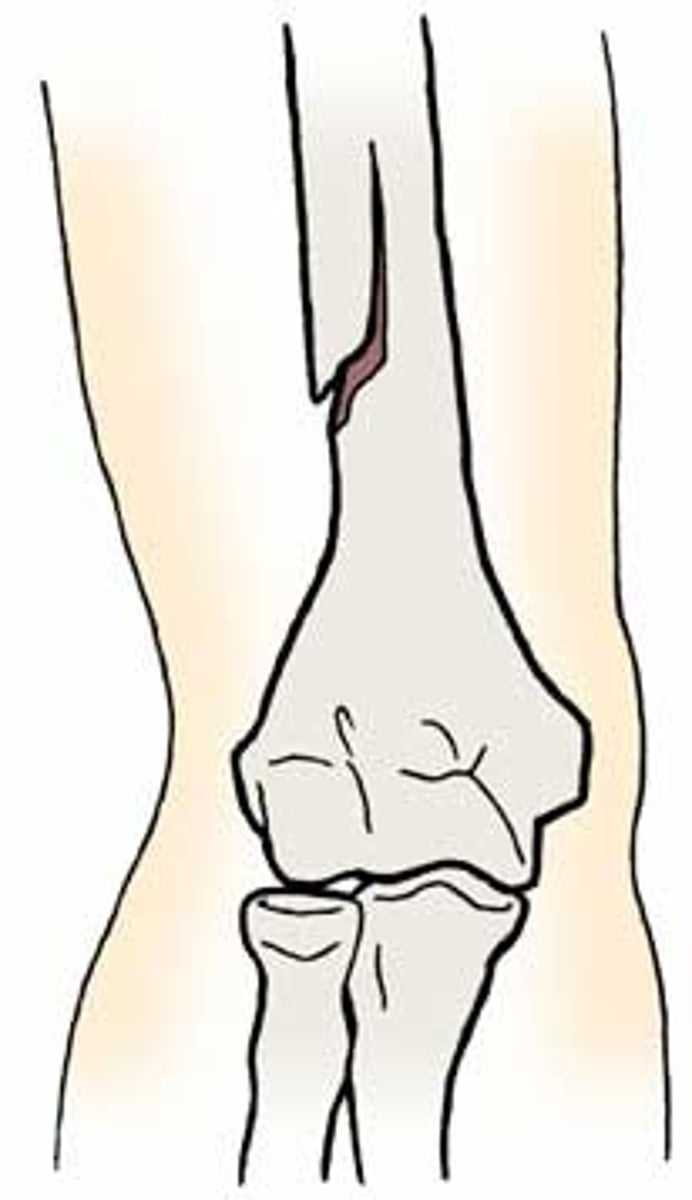

oblique fracture

occurs at an angle through the bone